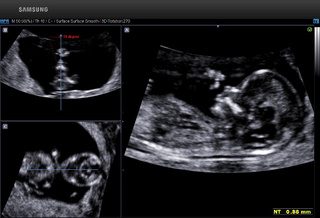

5D超声能够全方位、多角度评估胎儿生长发育情况,广泛应用于胎儿染色体异常所致畸形(NT测量)、胎儿长骨畸形、胎儿心脏畸形、胎儿中枢神经系统畸形等产前筛查的各个领域。

5D智能超声通过大样本的数据分析,智能识别胎儿产前筛查所需多种标准切面,自动进行多项数据测量。对胎儿畸形的早期诊断提供比传统四维彩超更精确的数据!

↓↓胎儿颈项透明层智能识别分析技术 ↓↓胎儿颅脑智能识别分析技术